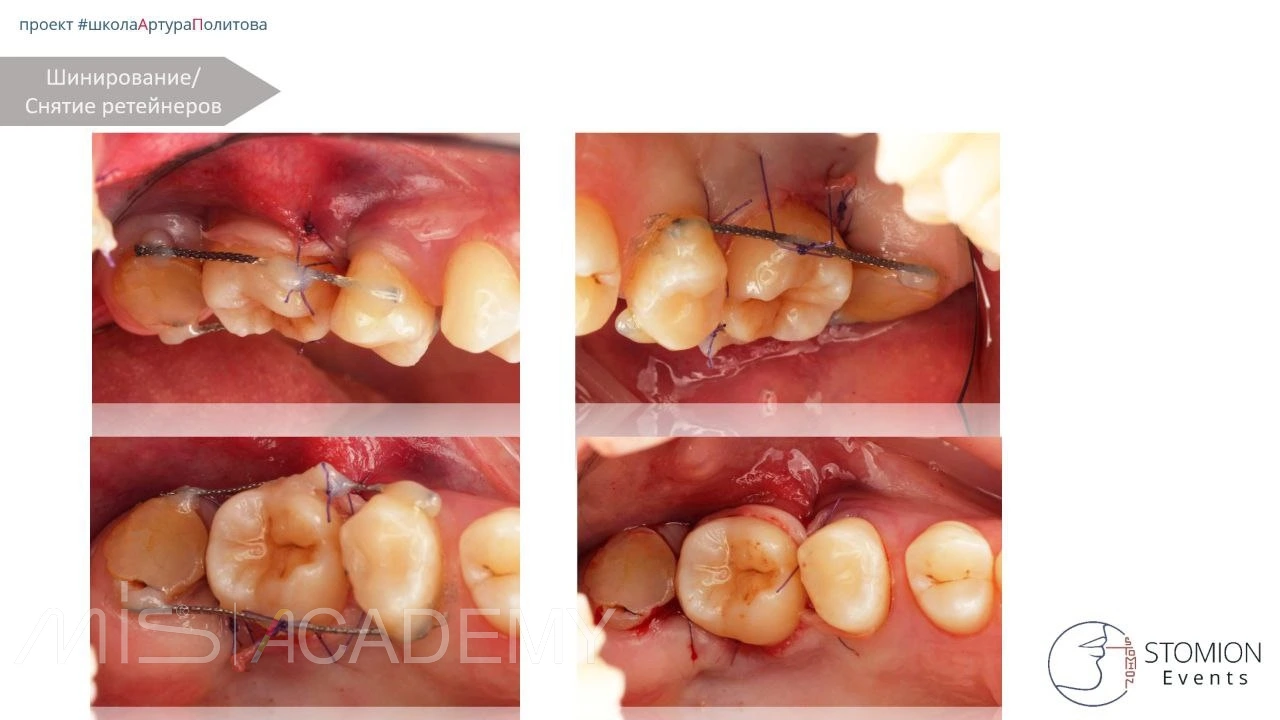

• Фиксация трансплантата двумя шинами, создание клапана наложением швов.

• Через 14 дней — снятие ретейнеров, депульпирование, наложение кальция.